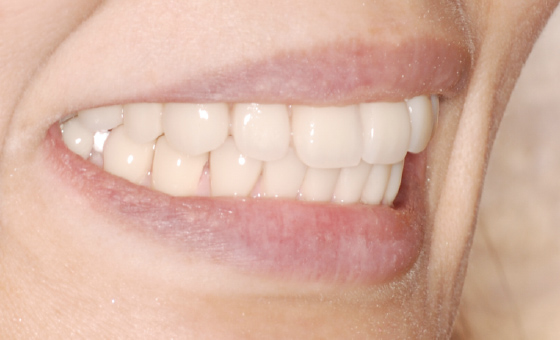

40代女性。歯科治療恐怖症で歯医者に通えず、噛み合わせが崩壊してしまい、オールオン4で再建した症例です。

オールオン4では、失われた歯茎も人工的に作りますので、お口の張りも回復させることができ、自然な美しい笑顔を作ることができます。